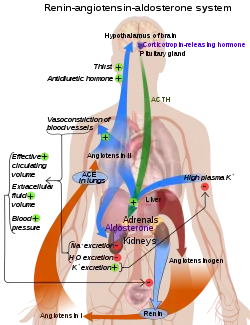

Angiotensin-converting enzyme (EC 3.4.15.1), or ACE, is a central component of the renin–angiotensin system (RAS), which controls blood pressure by regulating the volume of fluids in the body. It converts the hormone angiotensin I to the active vasoconstrictor angiotensin II. Therefore, ACE indirectly increases blood pressure by causing blood vessels to constrict. ACE inhibitors are widely used as pharmaceutical drugs for treatment of cardiovascular diseases.[5]

ACE is a central component of the renin–angiotensin system (RAS), which controls blood pressure by regulating the volume of fluids in the body.

Angiotensin II is a potent vasoconstrictor in a substrate concentration-dependent manner.[10] Angiotensin II binds to the type 1 angiotensin II receptor (AT1), which sets off a number of actions that result in vasoconstriction and therefore increased blood pressure.

ACE is also part of the kinin–kallikrein system where it degrades bradykinin, a potent vasodilator, and other vasoactive peptides.[12]

Kininase II is the same as angiotensin-converting enzyme. Thus, the same enzyme (ACE) that generates a vasoconstrictor (ANG II) also disposes of vasodilators (bradykinin).[11]

ACE inhibitors inhibit ACE competitively.[18] That results in the decreased formation of angiotensin II and decreased metabolism of bradykinin, which leads to systematic dilation of the arteries and veins and a decrease in arterial blood pressure. In addition, inhibiting angiotensin II formation diminishes angiotensin II-mediated aldosterone secretion from the adrenal cortex, leading to a decrease in water and sodium reabsorption and a reduction in extracellular volume.[19]